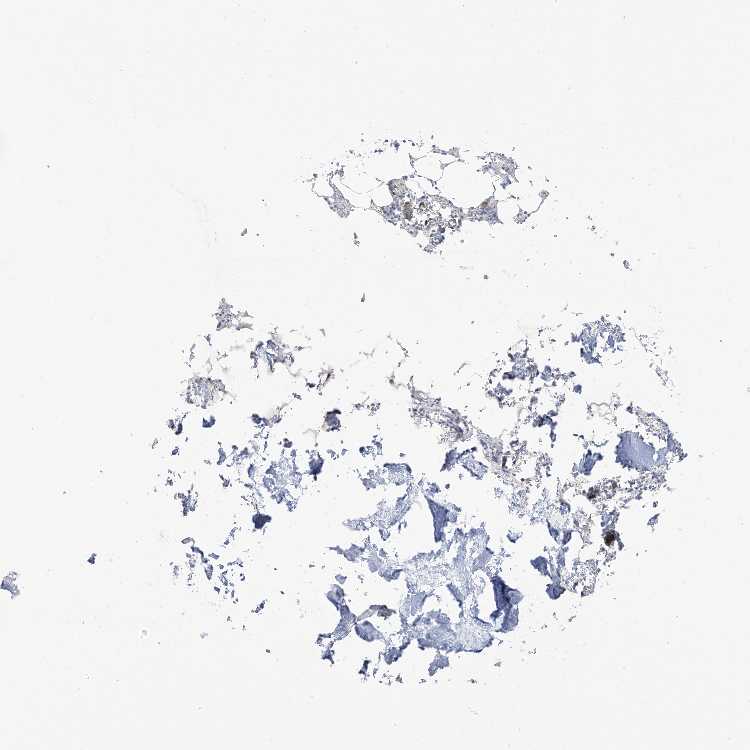

BONE MARROW - Antibody stainingi

Antibody staining in the annotated cell types in the current human tissue is reported as not detected, low, medium, or high, based on conventional immunohistochemistry profiling in selected tissues. This score is based on the combination of the staining intensity and fraction of stained cells.

Each image is clickable and will lead to virtual microscopy that enables deeper exploration of all samples and also displays staining intensity scores, fraction scores and subcellular localization as well as patient and tissue information for each sample.

Antibody HPA032014

Hematopoietic cells Low